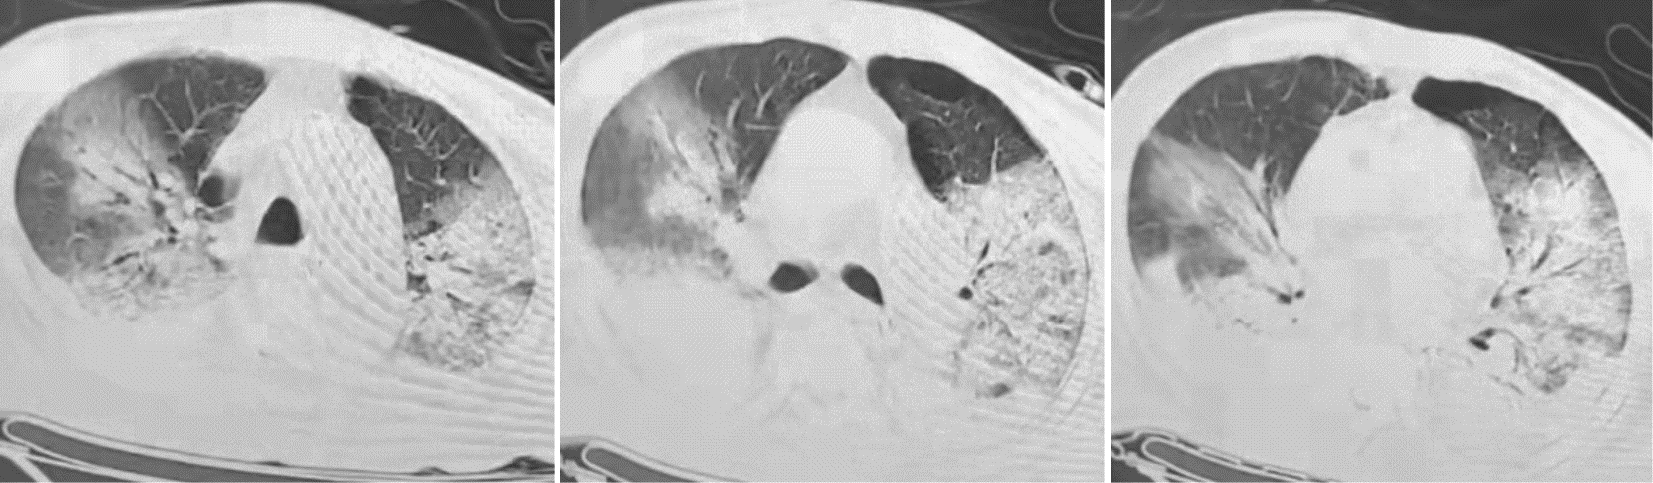

目的:探讨免疫功能正常的重症Ⅰ型单纯疱疹病毒(type Ⅰ herpes simplex virus,HSV-1)肺炎的诊治思路。方法:收集和回顾4例2021年4月至12月入住开云网页登录 医学院附属瑞金医院呼吸重症监护室(respiratory intensive care unit,RICU)诊断为重症HSV-1肺炎患者的诊治过程,并复习国内外相关文献。4例患者均为男性,年龄72~89岁。结果:4例患者以发热、咳嗽、咳痰(部分患者有血性痰)、气喘和呼吸困难为主要症状。患者均出现重度Ⅰ型呼吸衰竭,感染指标均上升,同时淋巴细胞计数相对下降,CD3、CD4、CD8绝对计数在治疗后均出现明显上升。呼吸道标本的宏基因组二代测序(metagenomic next generation sequencing, mNGS)中都检测到HSV-1。所有患者采用早期抗病毒、激素抗炎,呼吸支持治疗后,病情均好转,其中3例治愈出院。文献共检索到免疫力低下的HSV-1肺炎26例,免疫功能正常3例。29例患者的临床症状、体征缺乏特异性,经验性给予抗细菌或真菌治疗无效后,多数进一步完善肺泡灌洗液病原学检查,证实HSV-1感染后,积极给予阿昔洛韦抗病毒治疗,部分患者联合激素治疗,3例免疫功能正常者病情均好转,26例免疫力低下者中22例好转,4例死亡。结论高龄重症HSV-1性肺炎临床表现缺乏特异性,诊断存在一定难度。呼吸道分泌物mNGS检查联合常规实验室检查有助于该病的诊断。早期认识该病,予以抗病毒药物,短程使用糖皮质激素治疗可有效治疗该病。